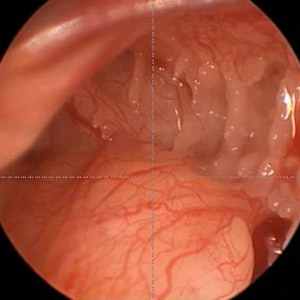

Endoskopischer Blick ins Hypotympanon